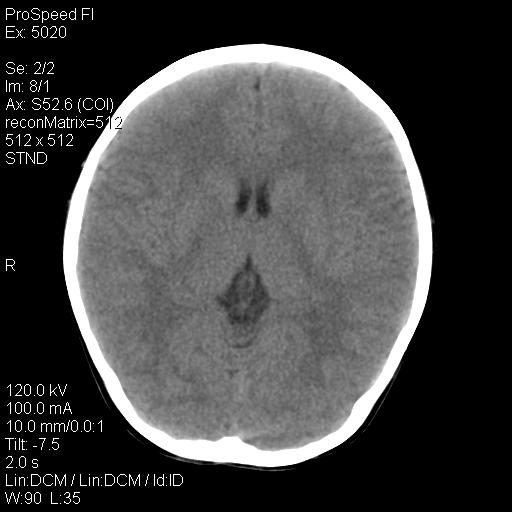

标题: PED1637:M 6Y 顶部无痛性包块两月。 [打印本页]

标题: PED1637:M 6Y 顶部无痛性包块两月。

2、颅骨局部缺失,边缘光滑、整齐

1、颅骨骨囊肿,以中青年多见,起源于骨内或骨膜下,常与外伤刺激有关。

2、颅骨皮样囊肿,皮样囊肿内为脂肪密度ct值多为负值,常在-15~10hu之间。

3、颅骨表皮样囊肿 病灶常有完整的包膜,ct值高低不等,可为脂肪密度至软组织密度,ct值常在-70—120hu之间。

颅骨的病损表现为内外颅骨板层不规则的锋利的破坏,形成“斜边缘”,有一定的特点

颅骨为好发部位,生长缓慢,常位于顶骨、枕骨及颞骨,表现为颅骨缺损,呈圆形或椭圆形,边界清,无硬化

事发冠状缝与矢状缝交界区,密度较低,考虑表皮样囊肿可能性大,其次不除外嗜酸性肉芽肿